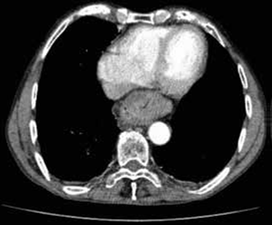

Se decidió ampliar el estudio con una tomografía computarizada (TC) de abdomen con contraste, en la cual se reportó una discreta dilatación esofágica en el tercio medio y proximal, acompañada de engrosamiento difuso de las paredes, y una hernia hiatal por deslizamiento con una porción del estómago ubicado en el mediastino posterior (figura 3).